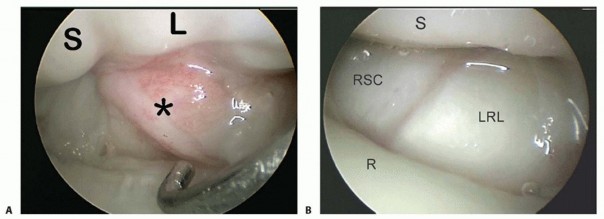

It is useful to have a systematic approach to viewing the wrist.The structures that should be visualized as a part of a standard examination include the radius articular surface; the proximal scaphoid, lunate, and triquetrum; the SLIL and lunotriquetral interosseous ligament (LTIL), both palmar and dorsal; the radioscaphocapitate ligament; the long radiolunate ligament; the radioscapholunate ligament; the ulnolunate ligament; the ulnotriquetral ligament; the articular disc; and the radial and peripheral TFCC attachments.Many procedures can be done without fluid, which minimizes the amount of swelling and fluid extravasation. Intermittentirrigation with a 10-mL syringe attached to the inflow portal of the arthroscope followed by suction with the full radius resector can help clear the field.The volar radial portal is used in patients with radial-sided and dorsal wrist pain to visualize the palmar SLIL and the DRCL.In patients with ulnar-sided wrist pain, the volar ulnar portal is used to assess the palmar LTIL and dorsal radioulnar ligament, the region of the ECU subsheath, and the radial TFCC attachment.The scope is then inserted in the 3-4 portal followed by various combinations of the 4-5 portal and 6R portal. The 6U portal is mostly used for outflow, but it may be used for instrumentation when débriding palmar LTIL tears.Midcarpal arthroscopy is then performed to probe the SLIL and LTIL joint spaces for instability, the capitohamate interosseous ligament, and to look for chondral lesions on the proximal capitate and hamate and loose bodies.The special-use portals such as the dorsal and volar DRUJ portals and the 1-2 portal are used as needed.